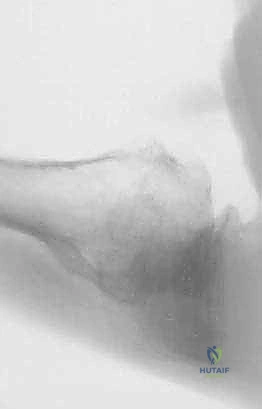

Radiographic findings in primary osteoarthritis include subchondral sclerosis and cyst formation, osteophyte formation, and asymmetrical posterior joint space narrowing ( FIG 4A,B ). 20

A B

A

B C

FIG 4 • Radiographic findings in osteoarthritis include osteophyte formation, especially on the inferior humerus as seen on the AP view ( A ), and asymmetrical posterior glenoid wear with posterior subluxation, as seen on the axillary view ( B ). C. CT scan reveals a large inferior humeral osteophyte and a type C glenoid, with increased glenoid retroversion. D. Coronal MR image in a patient with rheumatoid arthritis reveals an intact but very thin rotator cuff with erosion of the humeral attachment site, and evidence of rotator cuff dysfunction (ie, proximal humeral migration).

D

Computed tomographic (CT) scans are helpful in quantifying bone loss in patients with posterior subluxation ( FIG 4C ).

MRI is useful in patients with rheumatoid arthritis to determine rotator cuff integrity ( FIG 4D ).